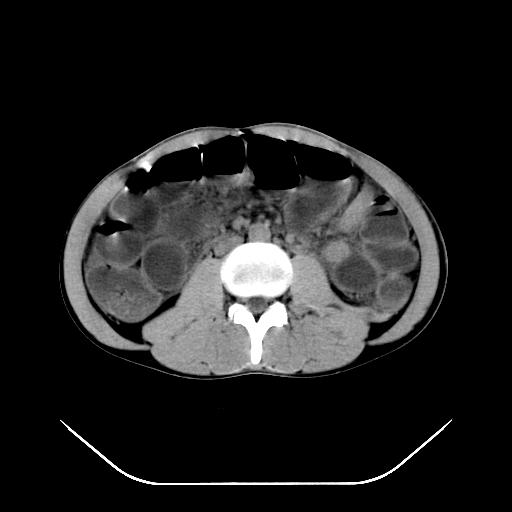

m-25y 高空堕落 12 月5号

12月7号病人尿量200ml/24h 急查双肾ct

左肾挫裂伤并肾周血肿;

左肾挫裂伤并肾周血肿

支持 : 左肾挫裂伤并肾周血肿

支持:1、左肾挫裂伤并肾周血肿;

2、少量腹水;

3、左肾旋转不良;

4、反射性肠淤张。

除了1:左肾挫裂伤并肾周血肿;

2:少量腹水

第二次ct检查后:临床医生腹水穿刺后考虑肠系膜动脉破裂,后实行剖腹探查:于空肠距离十二指肠90cm处发现肠管破裂,破裂口较小;修补后关腹。